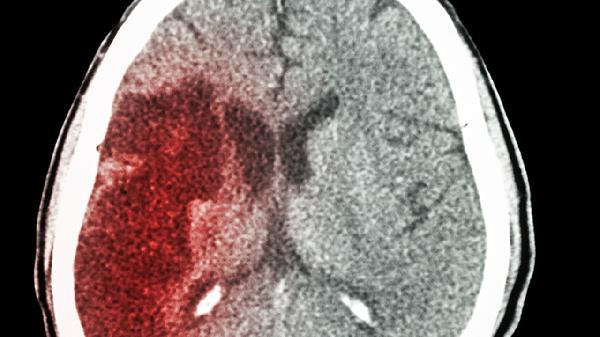

脑出血量直接影响预后,CT显示出血量小于30毫升且未累及脑干者,通过药物控制颅内压后,运动及语言功能恢复概率较高。超过50毫升的大面积出血常需手术清除血肿,术后可能遗留不同程度的偏瘫或认知障碍。

基底节区出血易导致对侧肢体瘫痪,但经6个月规范康复后约60%患者可恢复行走能力。脑干出血死亡率高达50%,幸存者多伴有长期吞咽障碍或平衡失调,需通过球囊扩张术联合吞咽训练改善。